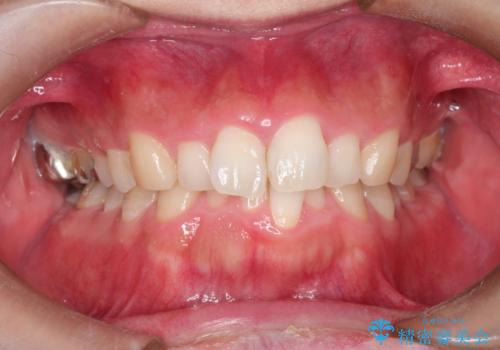

全体のガタガタをインビザラインできれいな歯並びへ